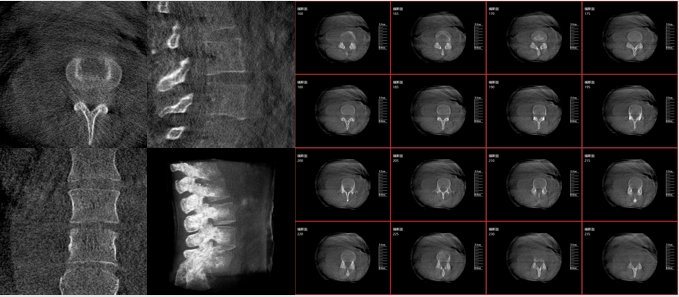

術中二維影像

從圖中可以看到二維影像能夠提供目標區域在某一個平面的重疊影像,雖然因為人體不同組織的密度差異,使得圖像具有較為豐富的信息量,但組織間的相互重疊還是會出現,諸如空間位置等眾多信息在影像中遺失或不可辨認的情況,影響了醫生對信息的收集與應用。

術中三維影像

而三維影像的MPR圖像組可以通過不同平面的切分,使成像區內更豐富的信息得以呈現。尤其是二維影像無法涉及的橫斷面,提供了另一個空間維度的信息量。